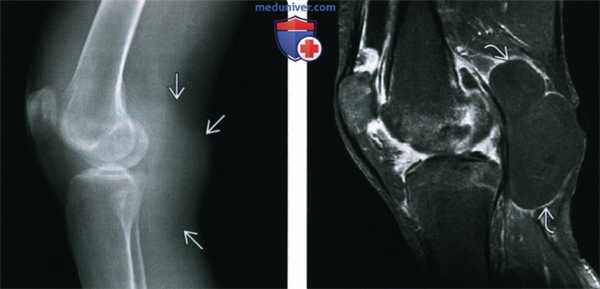

(Слева) Рентгенография в ПЗ проекции: признаки раннего РА у женщины 43 лет. Визуализируется общее умеренное истончение хряща и единичная эрозия. Можно думать об остеопении, однако признаки ее сложно оценить на ранней стадии заболевания.

(Справа) Рентгенография в боковой проекции: умеренное истончение хряща по всей площади у этой же пациентки. Над надколенником визуализируется значительное количество выпота и предполагается деминерализация ею нижнего полюса. Здесь процесс выглядит исключительно эрозивным, но недифференцированным. (Слева) МРТ, корональная проекция, режим Т1: подтверждается наличие единичной эрозии у этой же пациентки. Также обратите внимание на разрыв тел обоих менисков. Режим протонной плотности обеспечивает более точную визуализацию, по сравнению с режимом Т1, однако данный срез информативен.

(Справа) МРТ, аксиальная проекция, режим Т2 с подавлением сигнала от жира: в массивном выпоте визуализируются характерные для РА рисовые тела. Кроме того, надколенник фактически лишен хряща и визуализируются признаки формирования субхондральной кисты значительного размера. Такие признаки характерны для РА, диагноз был подтвержден серологически.